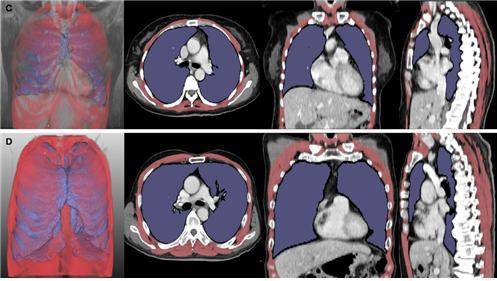

이러한 문제 해결을 위해 연구진은 인공지능(AI)을 이용, 루게릭병 환자의 폐와 호흡근육 위축 정도를 나타내는 폐 용적 지수(LVI)와 호흡근 용적 지수(RMI)를 개발했다. 그런 다음 루게릭병 환자 261명의 흉부 CT 영상을 분석, 루게릭병 병기‧생존기간과의 연관성을 확인했다. RMI는 폐와 호흡근의 부피를 키의 제곱으로 나눈 값이다.

연구진에 따르면, 폐·호흡근 용적 지수는 루게릭병 병기(1~4기)가 높아질수록 유의미하게 감소했고, 해당 지수를 통한 환자의 예후 평가 정확도는 기존 폐활량 검사와 큰 차이가 없었다. 폐·호흡근 용적 지수가 낮은 환자군은 높은 환자군보다 호흡근육 위축이 뚜렷했으며, 기관절개술을 받거나 사망에 이르는 시점도 빨랐다. 기관절개술은 호흡근육이 약해진 루게릭병 환자에게 시행하는 것으로, 목 부위를 절개해 인공 기도관을 삽입하는 수술이다.